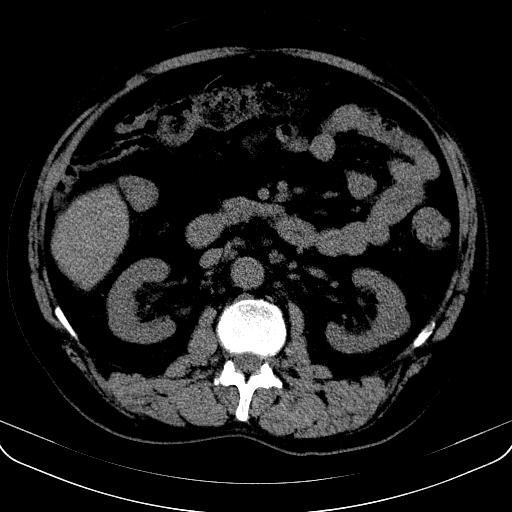

以下是引用jia119在2008-3-5 13:31:00的发言:[br]肝内多发片状低密度影,密度不均,我还是考虑肝ca可能,另肝内小囊肿,胆囊增大。

以下是引用形影不离在2008-3-5 12:18:00的发言:[br]肝硬化伴门脉高压征,肝内占位待排,增强再说.

以下是引用随光逐影在2008-3-5 21:11:00的发言:[br]肝硬化伴门脉高压(食管下段静脉曲张),肝癌不排除。建议:行ct增强扫描检查。

以下是引用同在2008-3-5 13:56:00的发言:[br]考虑肝癌可能性大,胆囊增大.